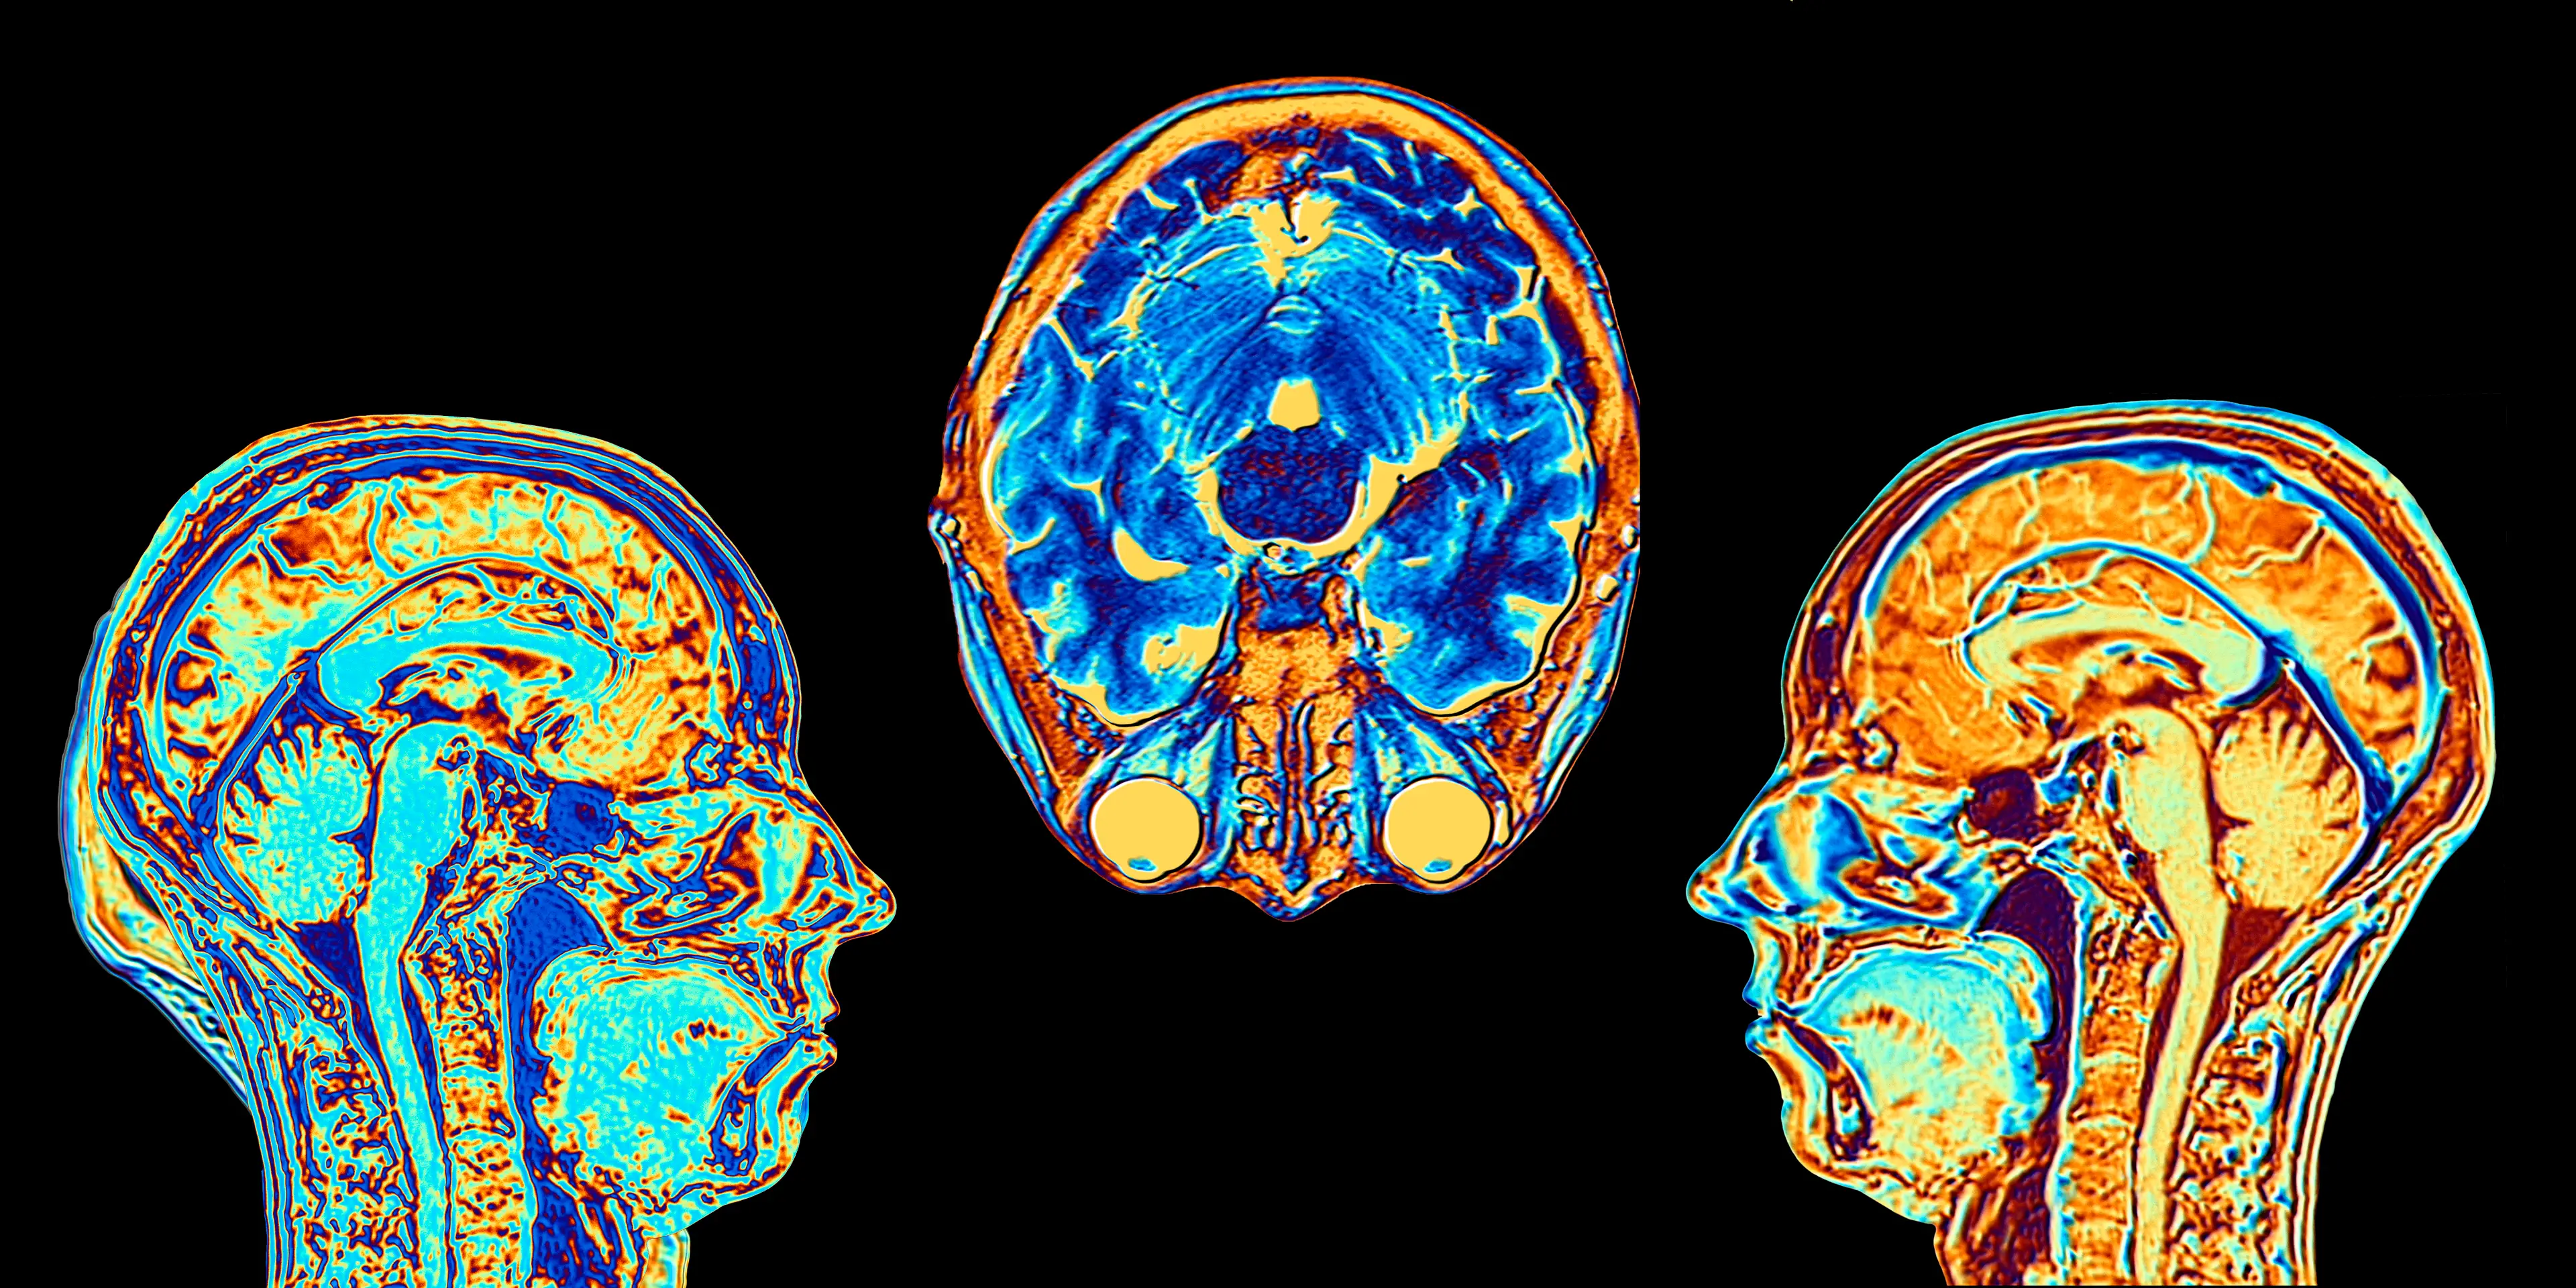

Researchers conducted high-resolution MRI scans in 46 adults who had used cannabis for at least 10 years and consumed it daily for at least five years.

And shockingly, scientists found that 'two areas of reduced cortical thickness' were identified in the 'right rostral middle frontal cortex' in long-term heavy cannabis users.